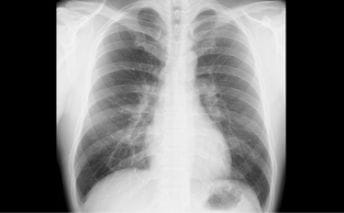

CT(コンピューターX線撮影)

CTはX線を使った人間の身体の透視画像を作ります。カメラが身体の周りをグルグル回り、輪切りの画像を何枚も撮り、単純な断層画像だけでなく、それらをつなぎ合わせて立体的な画像の作成もできます。

- 特長

- X線吸収差の大きい骨や肺の描出に優れている